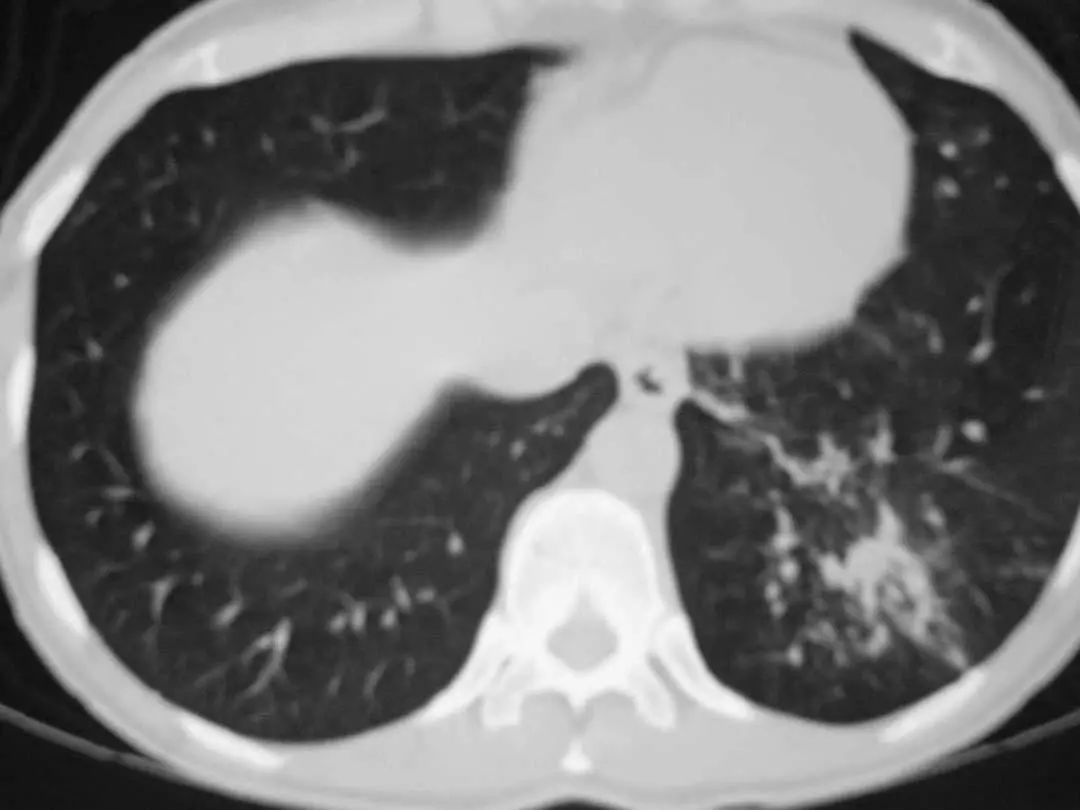

图1.7 CT扫描显示左下叶模糊的气腔浸润。